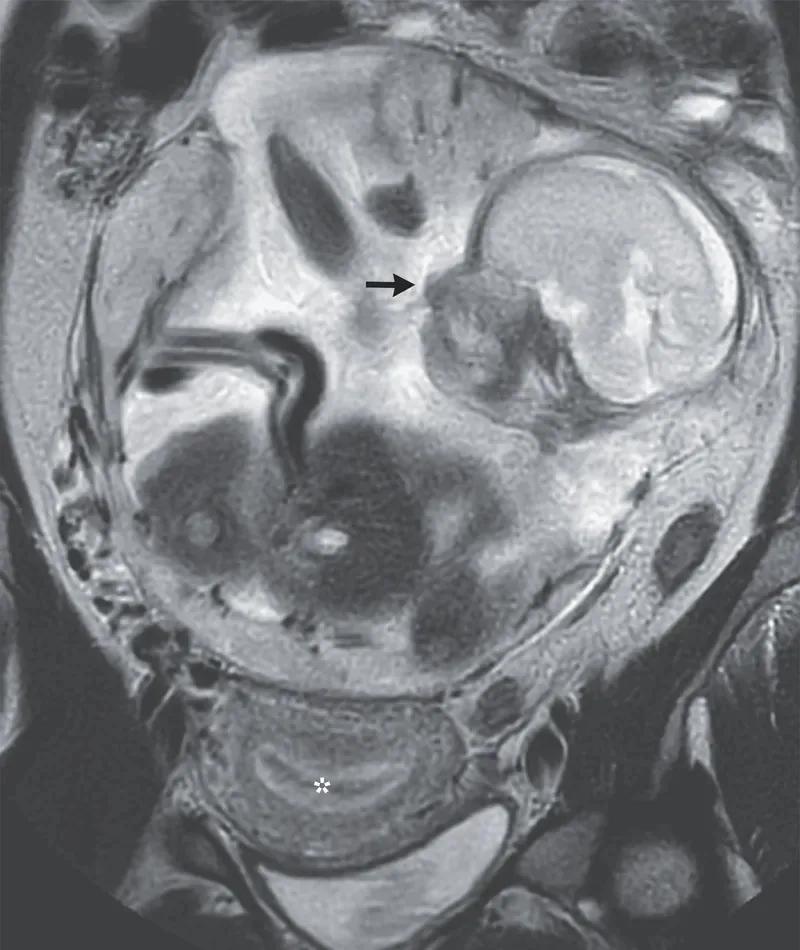

baby im darm gewachsen - Wie lang ist der Dünndarm Baby

baby im darm gewachsen - Wann hat sich der Darm beim Baby ausgereift